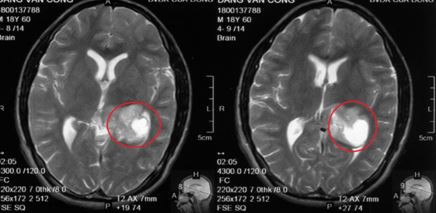

Bệnh nhân vào Bệnh viện Đa khoa tỉnh Nghệ An chụp cộng hưởng từ sọ não phát hiện có khối u lớn trong não (ở hồi hải mã trái), kích thước khoảng 30×35mm. Bệnh nhân được nhập viện Trung tâm Y học hạt nhân và Ung bướu, Bệnh viện Bạch Mai để điều trị tiếp.

Hình ảnh u não của bệnh nhân C

Kết quả giải phẫu bệnh sau mổ khối u não là Anaplastic Oligodendroglioma. Đây là khối u não ác tính nguyên phát tại não. Sau mổ 1 tháng, tình trạng ổn đinh, bệnh nhân được hội chẩn để điều trị hóa chất kết hợp với xạ trị.